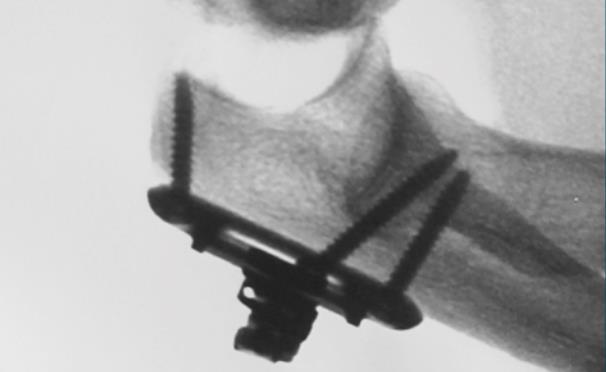

• Final fluoroscopic confirmation

• confirm that the reduction is maintained through the full ROM using fluoroscopic imaging

• Trimming the connecting rod

• using a pin cutter, remove any excess length from the Distal Connecting Rod that exits the Distal Locking Joint